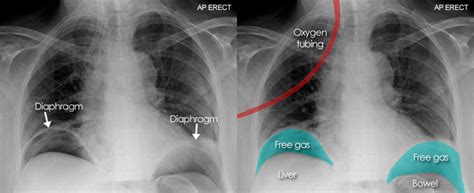

Chest Xray showing pneumoperitoneum (black arrow) and an abnormal gas